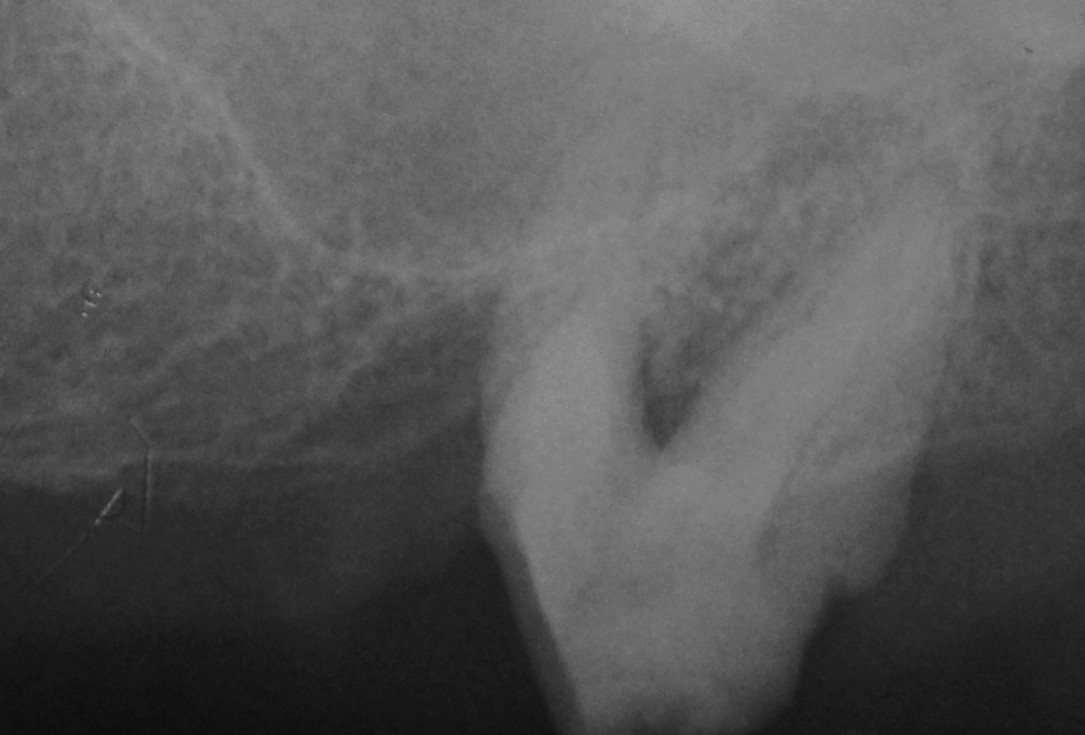

01/06 - Pre-operative radiograph.

Treatment of a periodontal bone defect adjacent to an edentulous site using Straumann® Emdogain® - Prof. Dr. P. Windisch